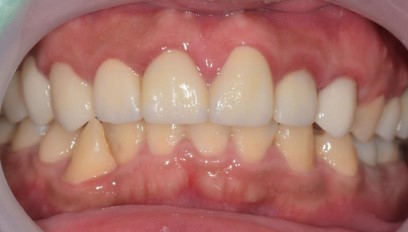

治療後 :套上假牙套+無牙根缺牙處靠牙橋復型,洗牙減緩牙齦發炎

牙根穩固了,牙周健康了,猶如樹根穩穩地抓住肥沃土壤,樹木自然能成長茁壯!!! 套上牙套調整咬合,恭喜您畢業了!!!!

假牙復型